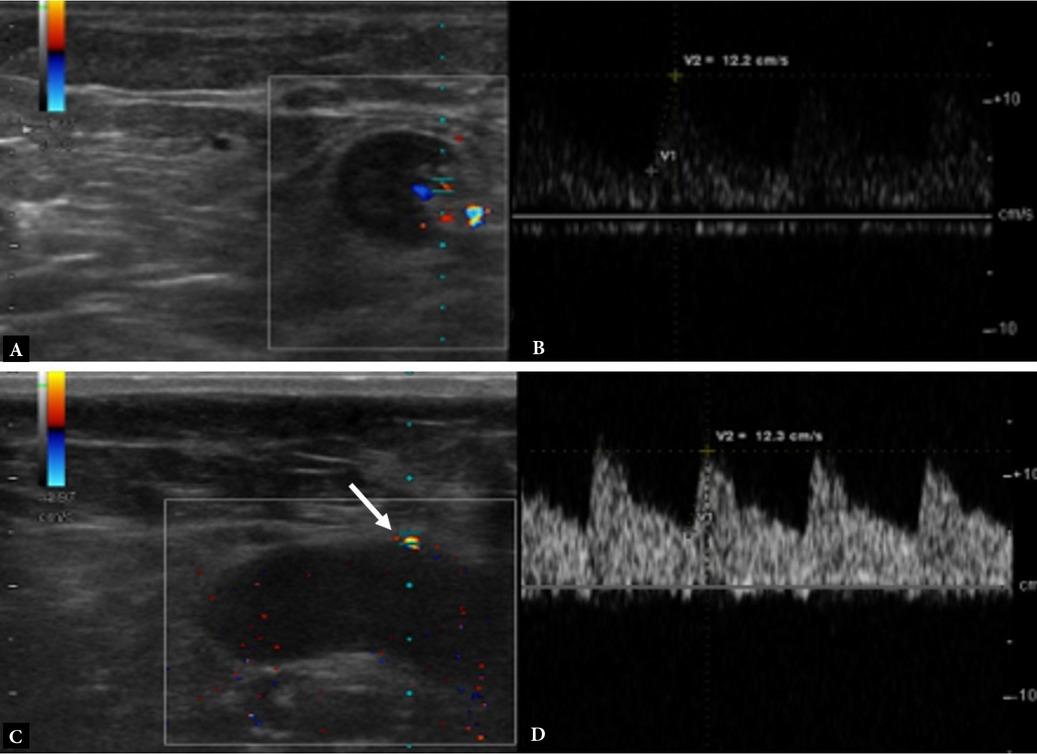

Fig. 1